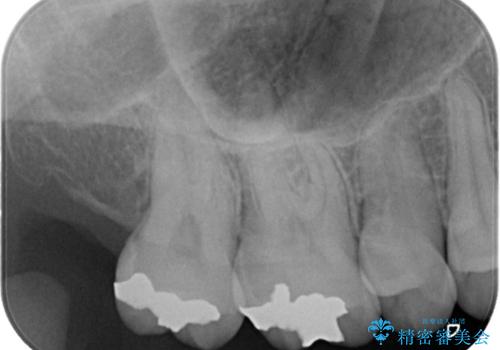

- 昔入れた金属の被せ物を白い物に変えたいと思い来院された患者様です。レントゲン等確認し審美的によく、強度のあるセラミックインレーにて治療いたしました。

審美的に良い補綴物に変わり満足いただきました。かみ合わせも問題なく快適に食事できているとのことでした。